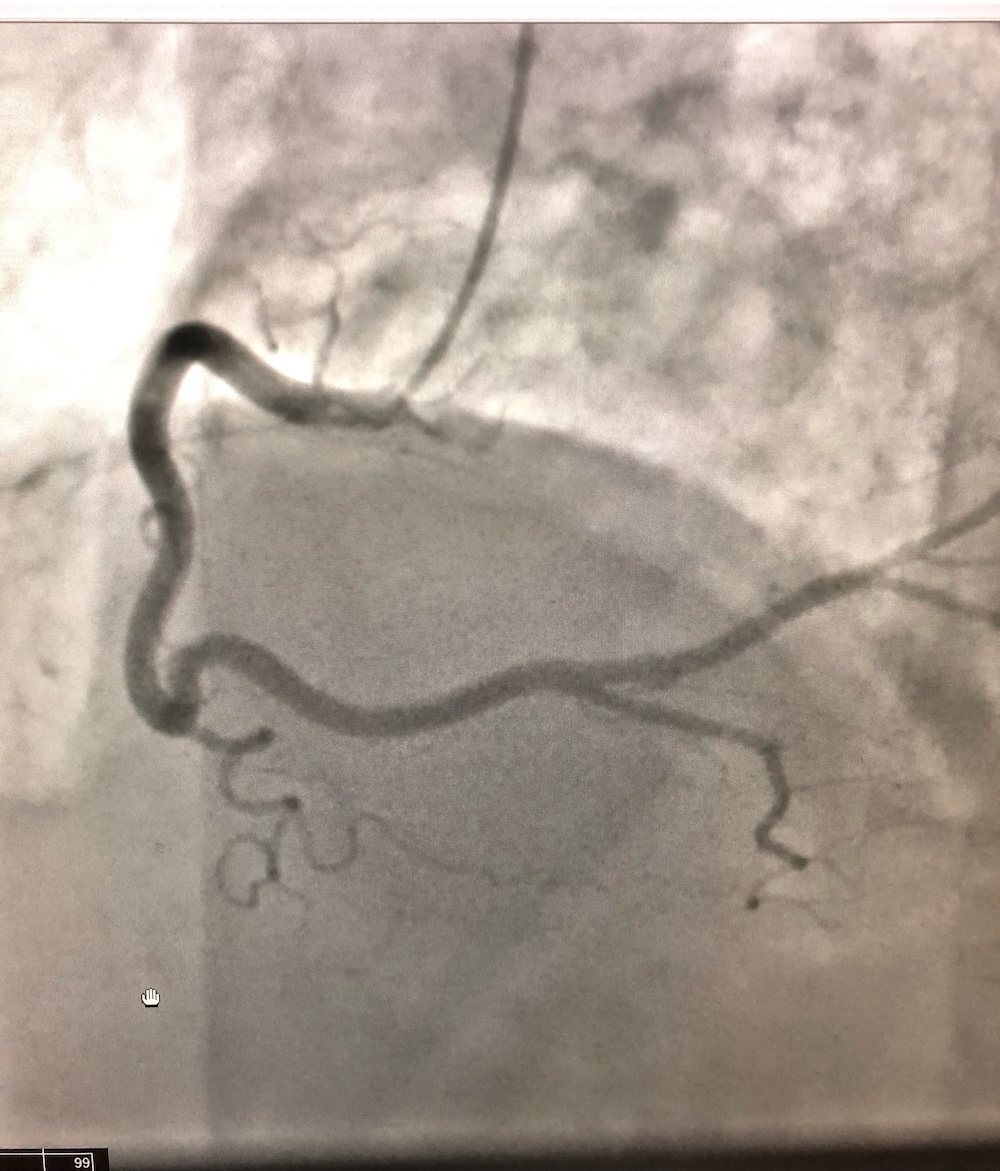

A cardiologist was consulted and recommended a left heart catheterization to evaluate this new-onset cardiomyopathy. Results of the catheterization revealed widely patent coronary arteries and confirmed nonischemic cardiomyopathy with an ejection fraction of 35% to 40% (Figures 1 and 2).

Figure 1. Patent left anterior descending artery

Figure 2. Patent right coronary artery